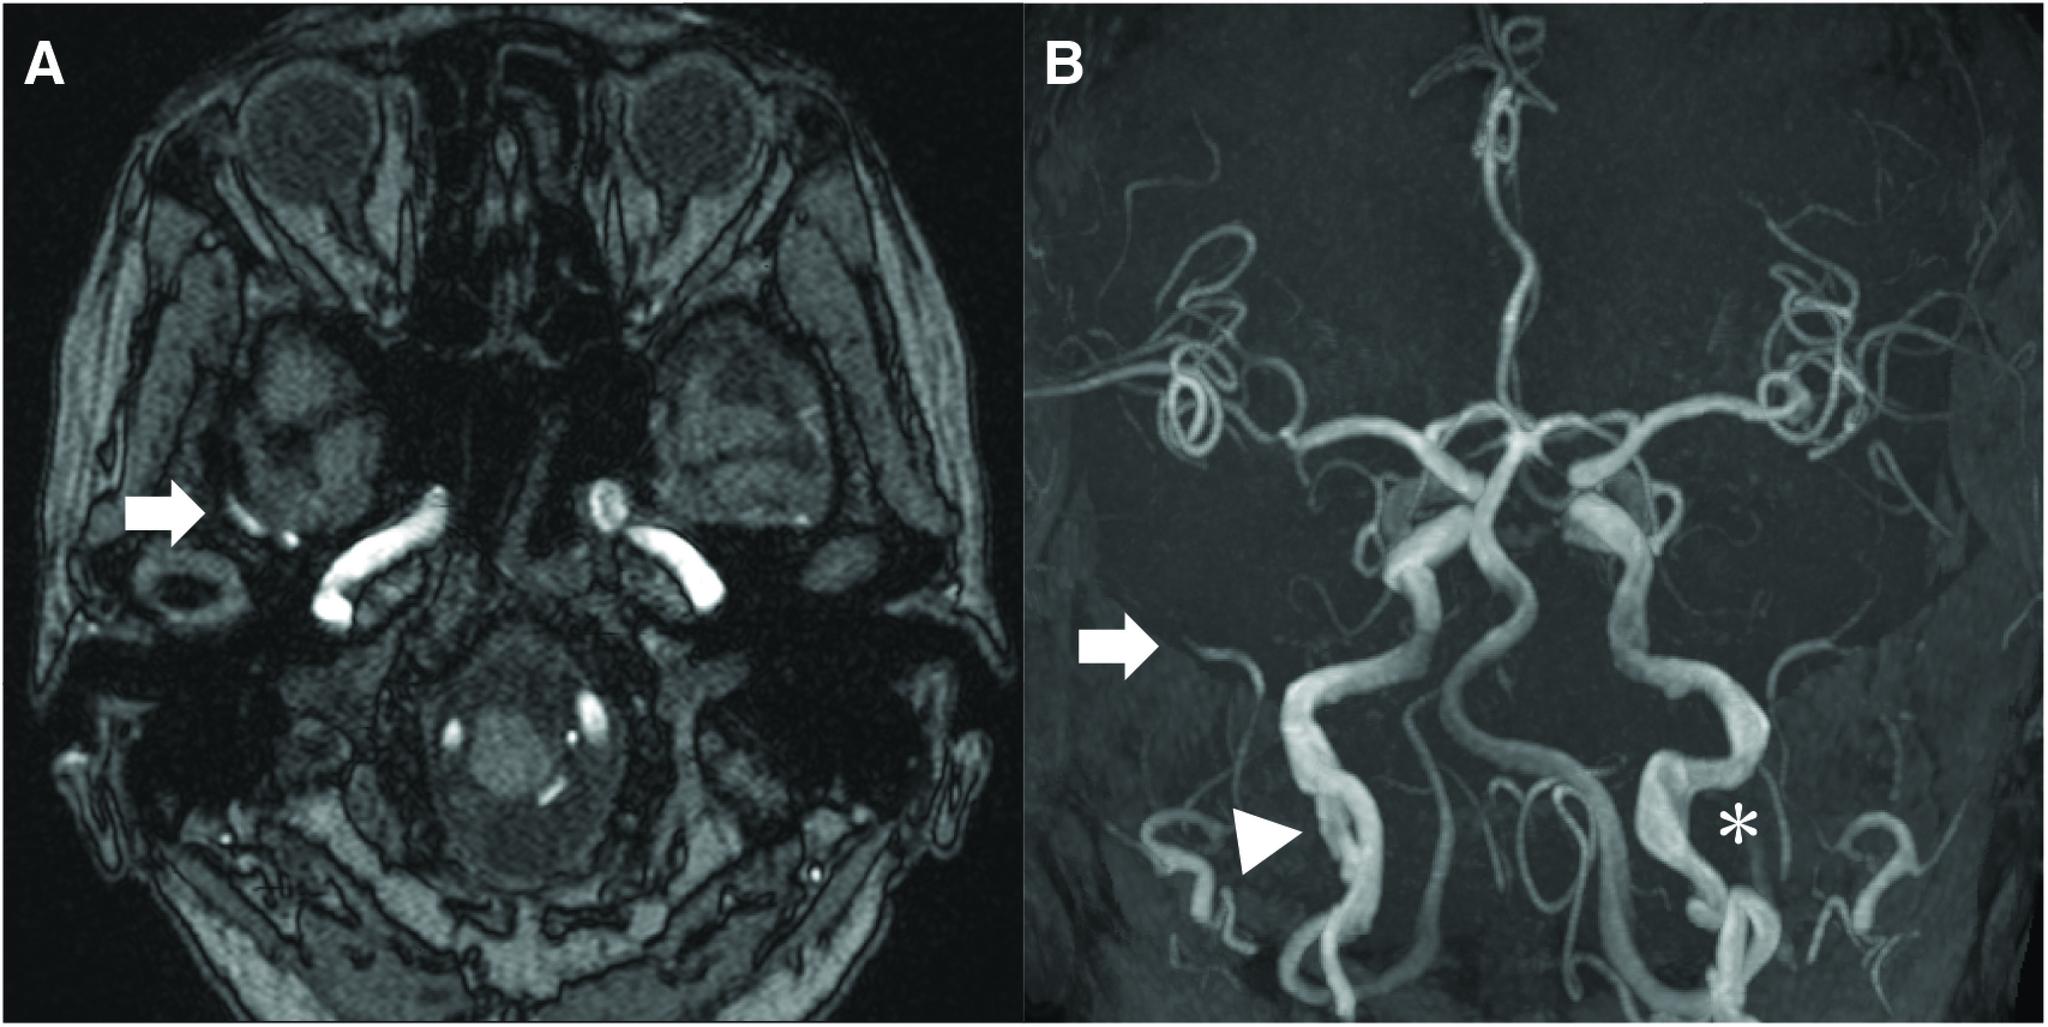

The patient was a 63-year-old woman admitted to our hospital with symptoms of right pulsating tinnitus for the past 2 months. She had no significant medical history. MRI and DSA revealed a right MMAVF. Selective embolization using coils was performed. Seven years later, when she underwent laparotomy for intestinal perforation, multiple aneurysms were found in the abdominal cavity. Left hemicolectomy was performed, and an aneurysm of the gastroepiploic artery was resected. Based on a pathological examination of the aneurysm, the patient was diagnosed with SAM. Coil embolization was performed to prevent rupture.

该患者为一名63岁女性,因过去2个月出现右搏动性耳鸣症状入院。她无重大病史。MRI和DSA显示右侧MMAVF。采用弹簧圈进行了选择性栓塞。7年后,当她因肠穿孔接受剖腹手术时,在腹腔内发现多个动脉瘤。进行了左半结肠切除术,并切除了胃网膜动脉的一个动脉瘤。根据动脉瘤的病理检查,该患者被诊断为SAM。进行了弹簧圈栓塞以防止破裂。